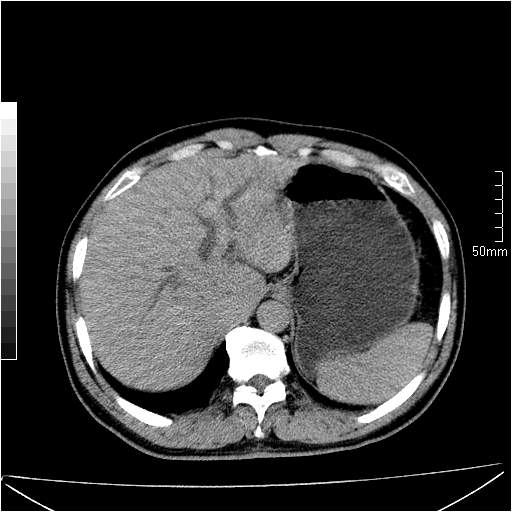

男性,54岁,皮肤黄染,搔痒一周余.b超示肝左叶回声异常.初步诊断1胆总管下段结石2胆囊结石伴慢性胆囊炎请各位战友帮忙看一下肝脏多发低密度如何解释恰当.增强效果不是很好.请大家见谅.

1、胆总管及肝内胆管扩张,(由于片子质量问题,不太好观察)。2胆囊癌?

胆总管及肝内胆管扩张,考虑是结石!但,肝内的低密度区增强不明,可能是肝ca,因为肝ca在增强时呈快进快出.另年胆总管扩张原因,可以考虑一下是不是,胆管ca.再次要考虑肝内的低密度是否为海绵状血管瘤所致!

首先,胆总管下端结石梗阻伴肝内胆管扩张可确定。

另外,肝八段低密度占位,呈多灶性,考虑肝脓肿或肝癌可能,(图像质量欠佳)建议进一步检查。

既然做了增强,为什么光提供延时期片子,肝动静脉期肝右叶前下段病灶增强如何?另外胆囊壁增厚,欠规整,内密度不均,与肝右叶病灶分界不清,增强表现怎样?肝内胆管轻度扩张,胆总管扩张,但未见明显结石影,也应提供增强早期图像才好鉴别扩张原因。片子较清,但不够完整,暂考虑1.胆囊癌肝局部浸润,或肝癌胆囊侵犯,2.胆总管下端或胰头钩突部占位。总之本人看不明白,请高手画图指示,先谢了!

由于胆囊窝内结构显示不清,肝脏病灶又邻近胆囊窝首先考虑胆囊癌肝受侵犯。而后因肝脏病灶强化有渐进改变,且相邻胆管扩张,故考虑肝胆管细胞癌待排。

左肝胆管细胞癌。

胆总管下端结石。